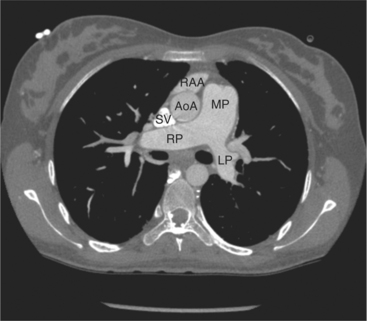

FIGURE 5-10 Images obtained from the patient in Figure 5-9. A, Axial acquisition through the main (MP) and left (LP) pulmonary artery. The preaortic recess is a fluid attenuation collection (arrow 1) between the ascending aorta (AoA) and MP. Similarly, the superior pericardial recess (arrow 2) is the fluid attenuation space between the superior vena cava (SV), AoA, and proximal right pulmonary artery (RP). The right upper lobe pulmonary vein (arrow 3) lies anterior to the prehilar right pulmonary artery, and the left upper lobe pulmonary vein (arrow 4) lies anterior to the left upper lobe pulmonary artery (arrow 5). The left bronchus (LB) and right bronchus (RB) are labeled. B, Right anterior oblique sagittal reconstruction from the patient in Figure 5-9 through the right ventricular outflow (RVO) and the aortic root (Ao). The pericardium (arrowheads) is a thin line separating the epicardial and pericardial fat. A small amount of fluid (double white arrows) has accumulated over the right ventricular sinus, increasing the width of the pericardial space. The preaortic recess (arrow 1) is a homogeneous fluid density bounded by the Ao, the RVO, and the reflection of the pericardium over the pulmonary artery and onto the aorta. The distal right coronary artery (arrow 2) runs in the inferior aspect of the anterior atrioventricular ring. The proximal right coronary artery (arrow 3) and the proximal portion of the conus branch (arrow 4) run embedded in fat in the superior aspect of the anterior atrioventricular ring. The suprahepatic inferior vena cava (IVC) enters the right atrium (RA) from its posterolateral aspect.

FIGURE 5-70 Axial acquisition through the main (MP), left (LP), and right (RP) pulmonary arteries from a contrast-enhanced examination in the 24-year-old woman in Figure 5-67. The MP is greater in caliber than the ascending aorta (AoA), indicating increased pulmonary blood flow or resistance. The right atrial appendage (RAA) and superior vena cava (SV) are also labeled.